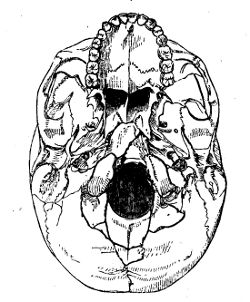

| InjuFractures of the Cranial Bones | 227 |

| Fracturesof the Cranium and Face | 558 |